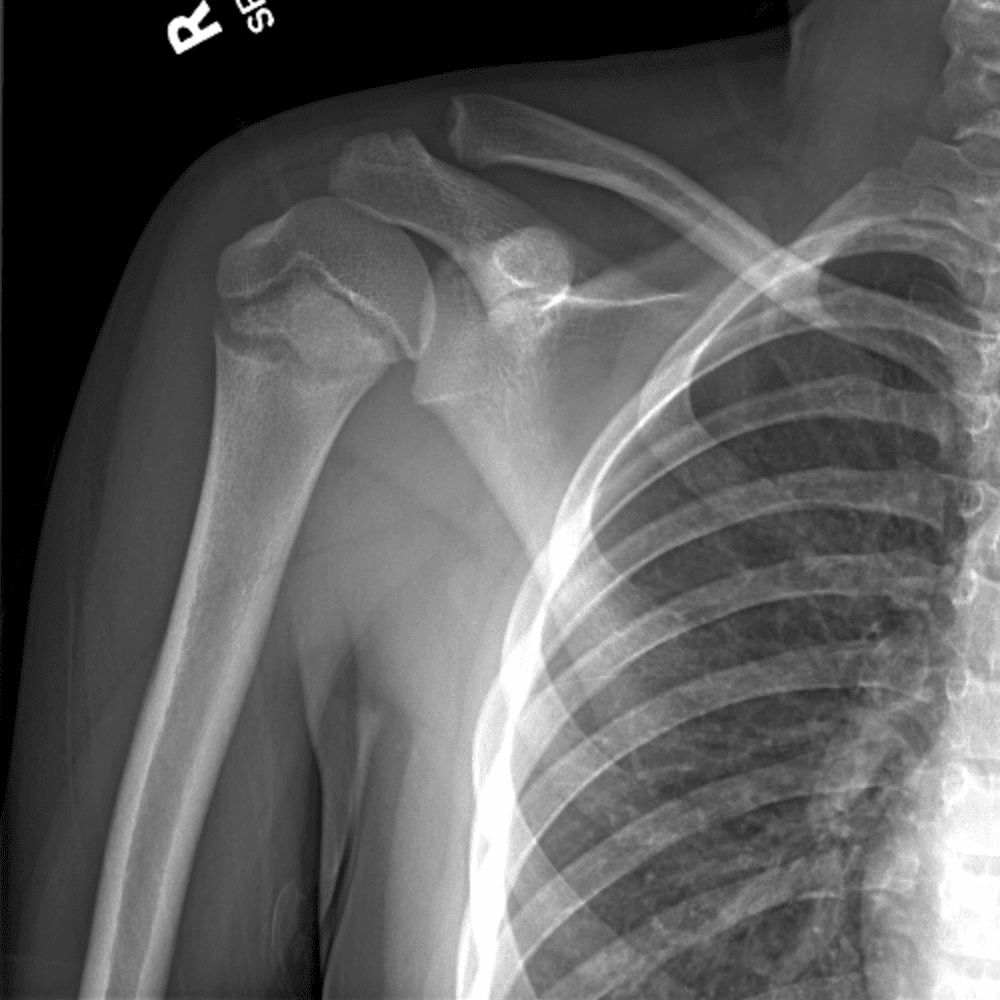

Simuliert den Dienst durch subtile oder schwierige Fälle und einige Normalbefunde.

30 Fälle